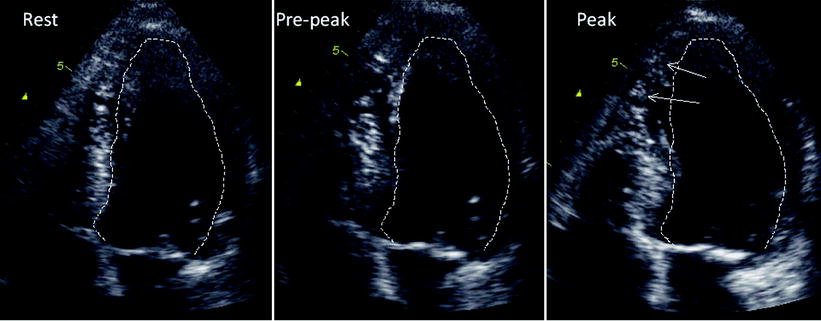

Echocardiography coronary artery disease. Stress echocardiography today has matured into a robust and reliable technique not only for the diagnosis of suspected coronary artery disease CAD but also for the accurate risk stratification of patients with suspected and established CAD. One of these approaches is the recording of abnormal wall motion. It is a tool which helps in reaching an early diagnosis of myocardial infarction showing regional wall motion abnormality of the heart.

PURPOSE OF REVIEW This review highlights recent progress in the quantitative approach to the interpretation of stress echocardiograms. The main objective of this report is to review the echocardiographic techniques used to image the coronary arteries of children when screening for anomalous origin of the coronary arteries as well as coronary involvement in the setting of Kawasaki disease.